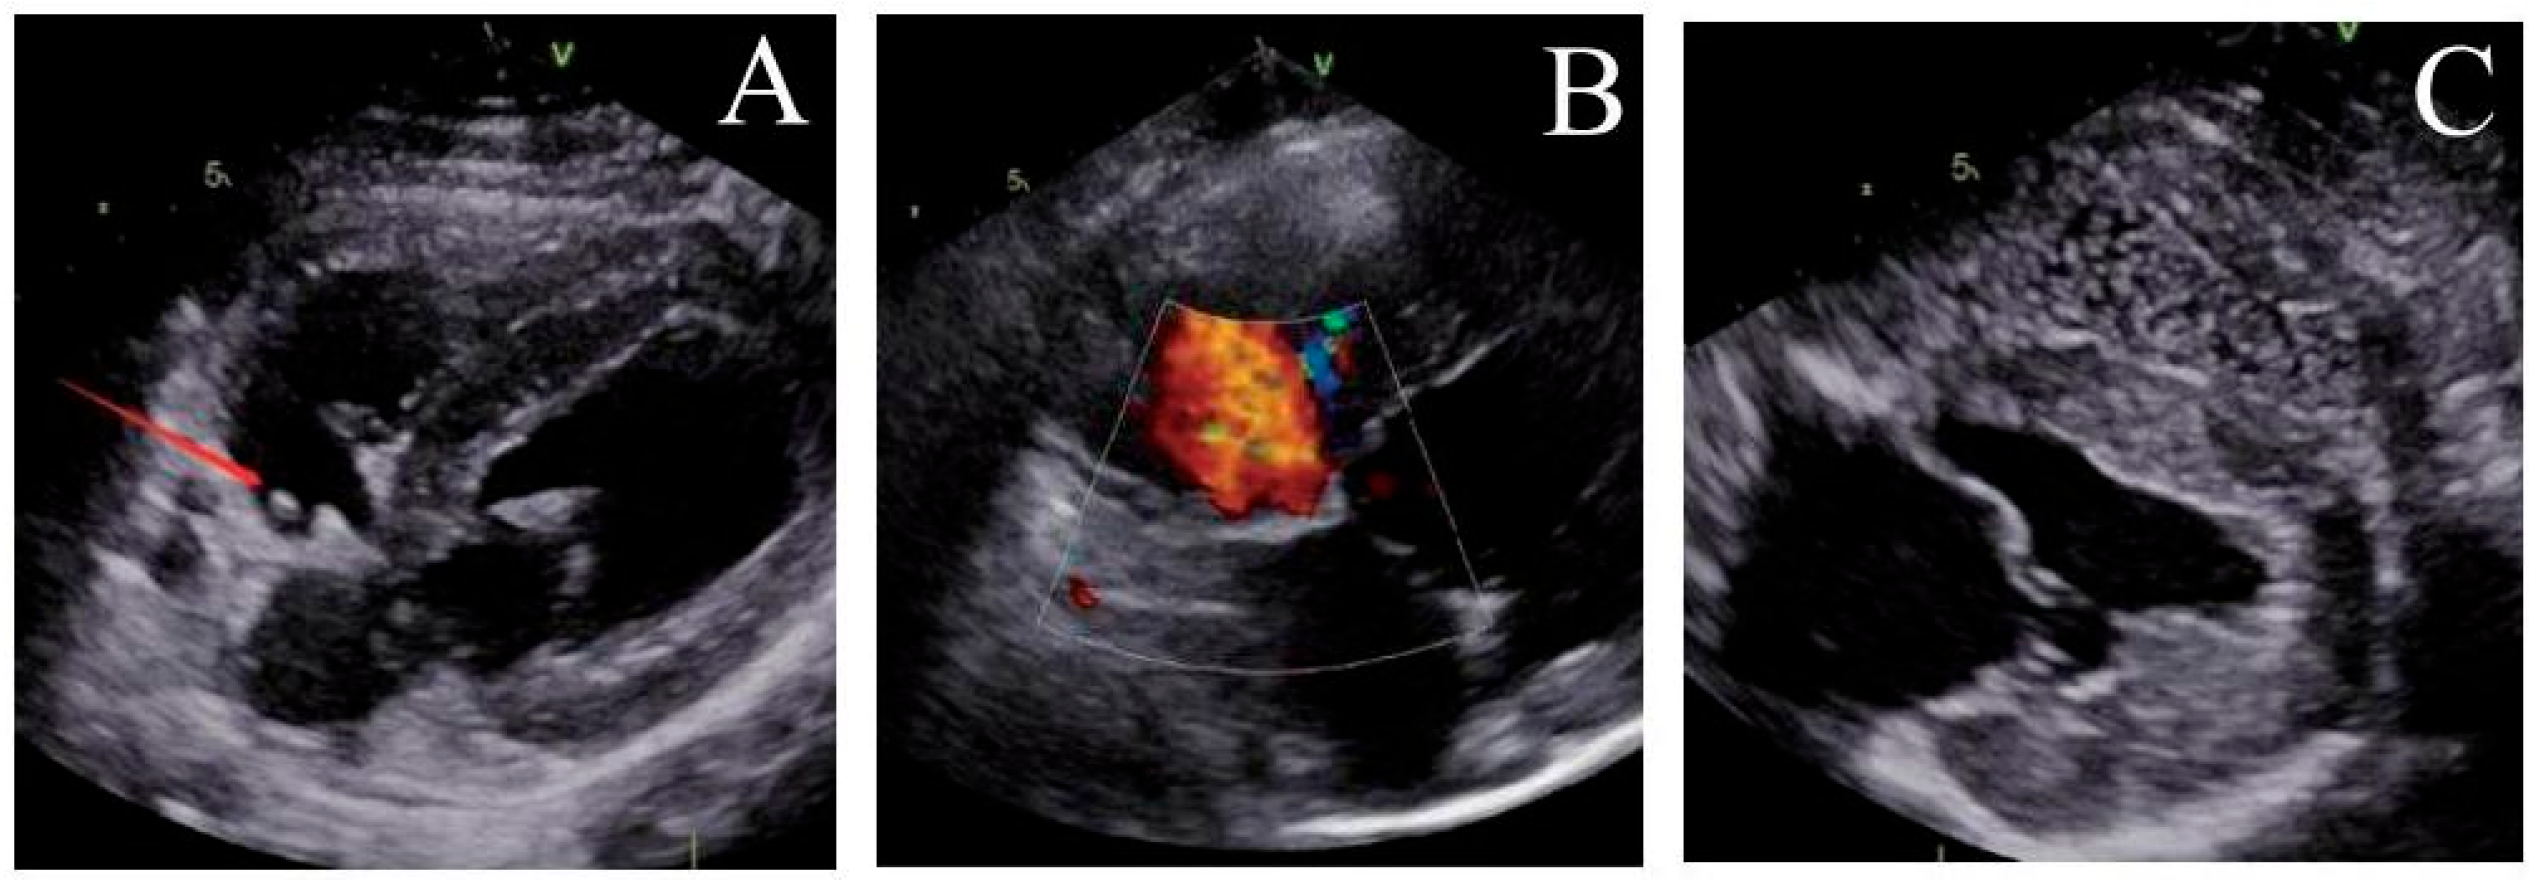

Post-implantation, the locking mechanism remained stable without suture breakage, thrombus formation, or neoplastic changes. The locking device was clearly visualized on ultrasound. Both the atrial septal defect diameter and residual shunt flow velocity decreased significantly over time, with near-complete defect closure observed by 6 months (postoperative ultrasound at immediate, 1, 3 and 6 months respectively, Fig. 3, Fig. 4, Fig. 5 and Fig. 6). Left ventricular hemodynamics and function remained unaffected.

4.2 Foramen Ovale Healing and Thrombus Incidence

The ultrasound follow-up results from our study showed a progressive decrease in the size of the foramen ovale injury over time, culminating in complete healing by six months. Correspondingly, the reflux velocity through the foramen ovale gradually diminished until it ceased entirely. During the operation and postoperative follow-up, no instances of neoplasm or thrombosis was observed under ultrasound. Gross anatomical examination revealed no thrombus formation on the surface of the suture or locking nail. Also, there were no infarcts detected in the core organs of the animals, including the heart, liver, spleen, lungs, kidneys, and brain.